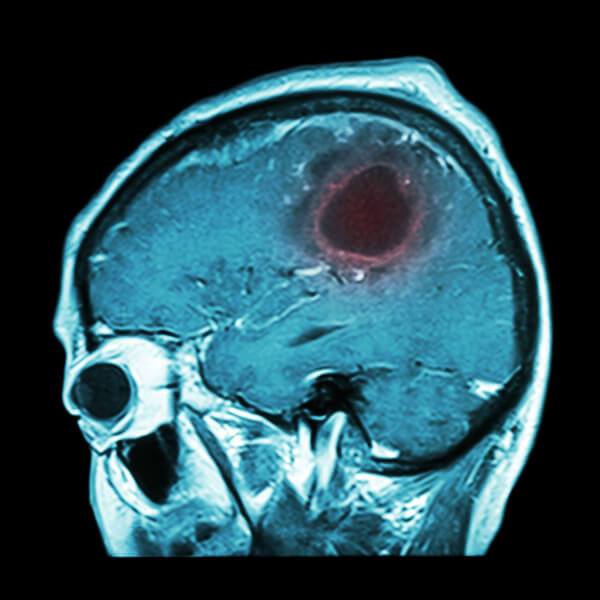

뇌종양

전신에서 발생하는 종양 중 세 번째로 많이 발생하는 뇌종양. 뇌종양의 가장 흔한 증상은 두통이다. 뇌종양의 두통은 종양이 인접한 뇌수막이나 혈관을 압박하고 팽창시키거나, 종양이 상당한 크기로 자라 뇌압이 상승하여 뇌수막을 자극하게 되면서 발생하게 되는데, 주로 새벽이나 아침에 심한 양상을 보인다.